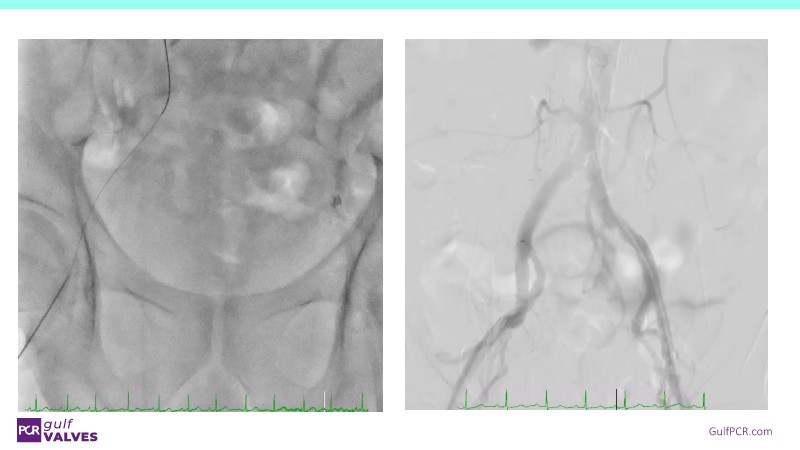

Discover a selection of cases showcasing the key features of the Navitor Valve System and its clinical applications. This session explores auxiliary access, the use of Navitor in alternative access and complex PCI, its performance in challenging peripheral anatomies, and innovative outcomes with the Vantage 30D system.